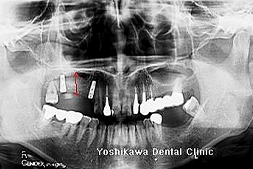

こちらの患者様は2002/02/21、16年前に当医院で私がインプラント手術致しました。

16年後の定期健診でインプラント周囲炎を起こしていることを発見致しました。

レントゲン上で左のインプラント周囲の骨が吸収しているのが観察されます。(2018年2月撮影)